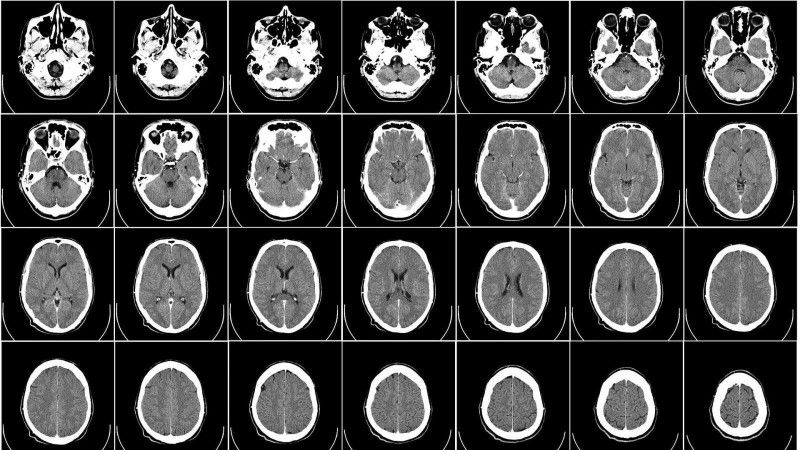

Применение МРТ в медицине

В настоящее время МРТ (рис. 4) широко используется в медицине. Посредством этого метода решаются две задачи. Первая задача состоит в визуализации внутренних органов (сердца, печени, легких, поджелудочной железы, почек), а также головного мозга, сосудов, позвоночника для определения их формы, размеров, расположения.

Вторая задача состоит в определении посредством МРТ характеристик биологических тканей (то есть тех или иных физических, физико-химических и иных свойств биологических тканей) и характера их функционирования.

В настоящее время сложились определенные направления использования МТР в медицине. Так, функциональная МРТ позволяет определять индивидуальное местоположение и особенности областей мозга, отвечающих за движение, речь, зрение, память и другие функции человека. Магнитно-резонансная ангиография позволяет изучать просвет кровеносных сосудов головного мозга. МРТ позвоночника применяется нейрохирургами для определения грыж межпозвонковых дисков и степени нестабильности позвоночника (рис.5).